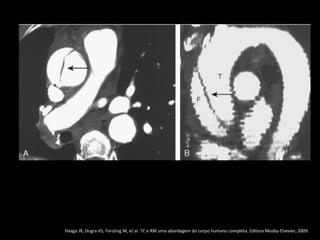

Definição da luz

•A luz falsa com frequência tem área transversal

maior devido ao fluxo lento;

• A luz verdadeira encontra-se comprimida em 80%

dos casos;

• A falsa luz tem maior propensão à trombose;

• Quando uma luz envolve a outra, a luz interna

invariavelmente é a verdadeira;

• O fluxo sanguíneo lento leva a retardo na

opacificação da luz falsa.

Sinal Mercedes-Benz

Multidetector CT of Aortic Dissection: A Pictorial Review 1. Radiographics march-april, 2010.